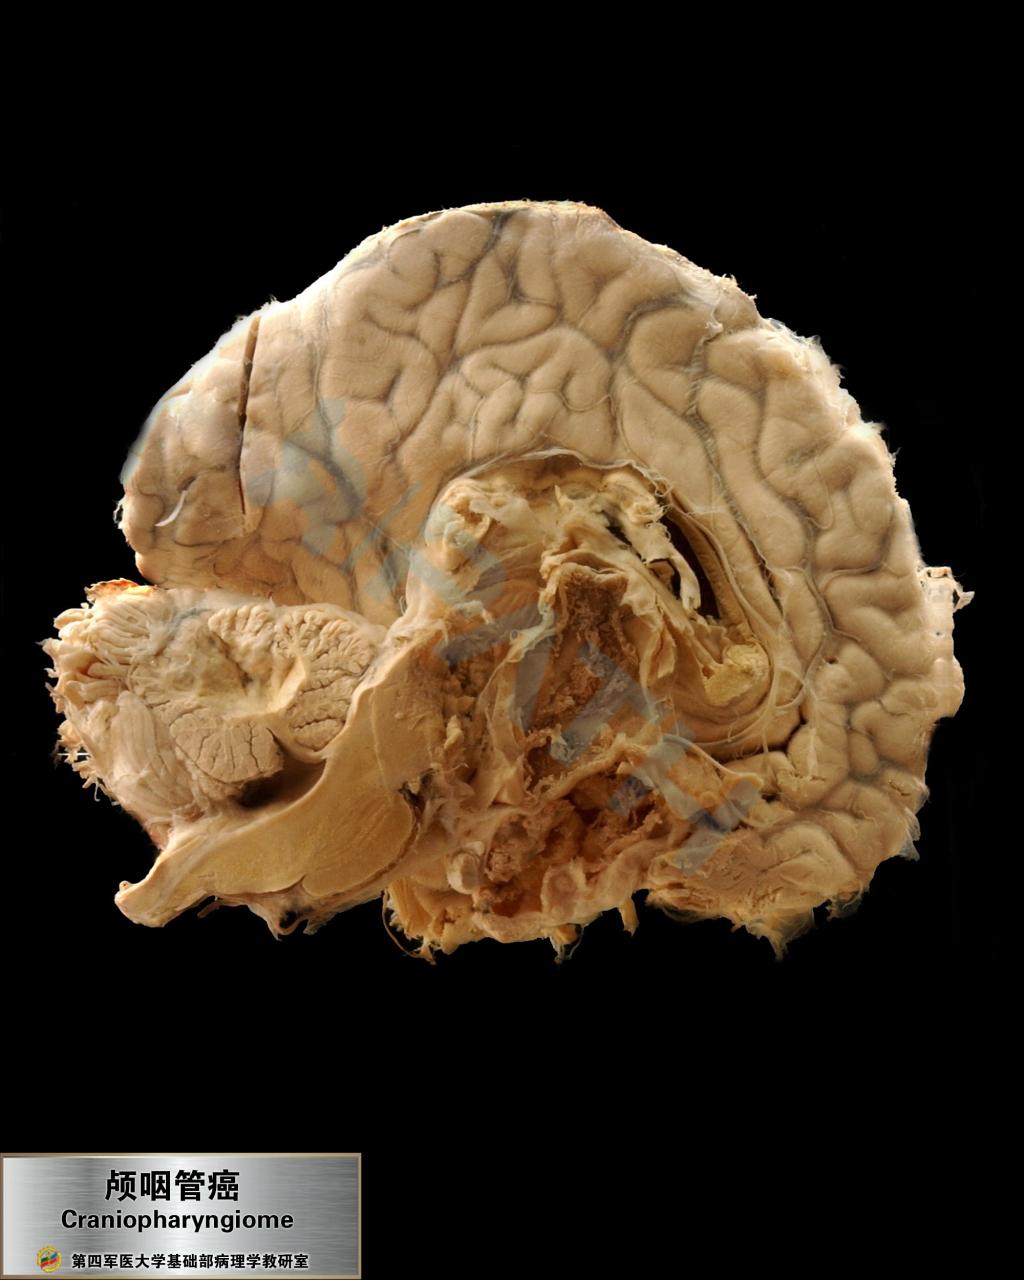

颅咽管瘤

神经系统疾病